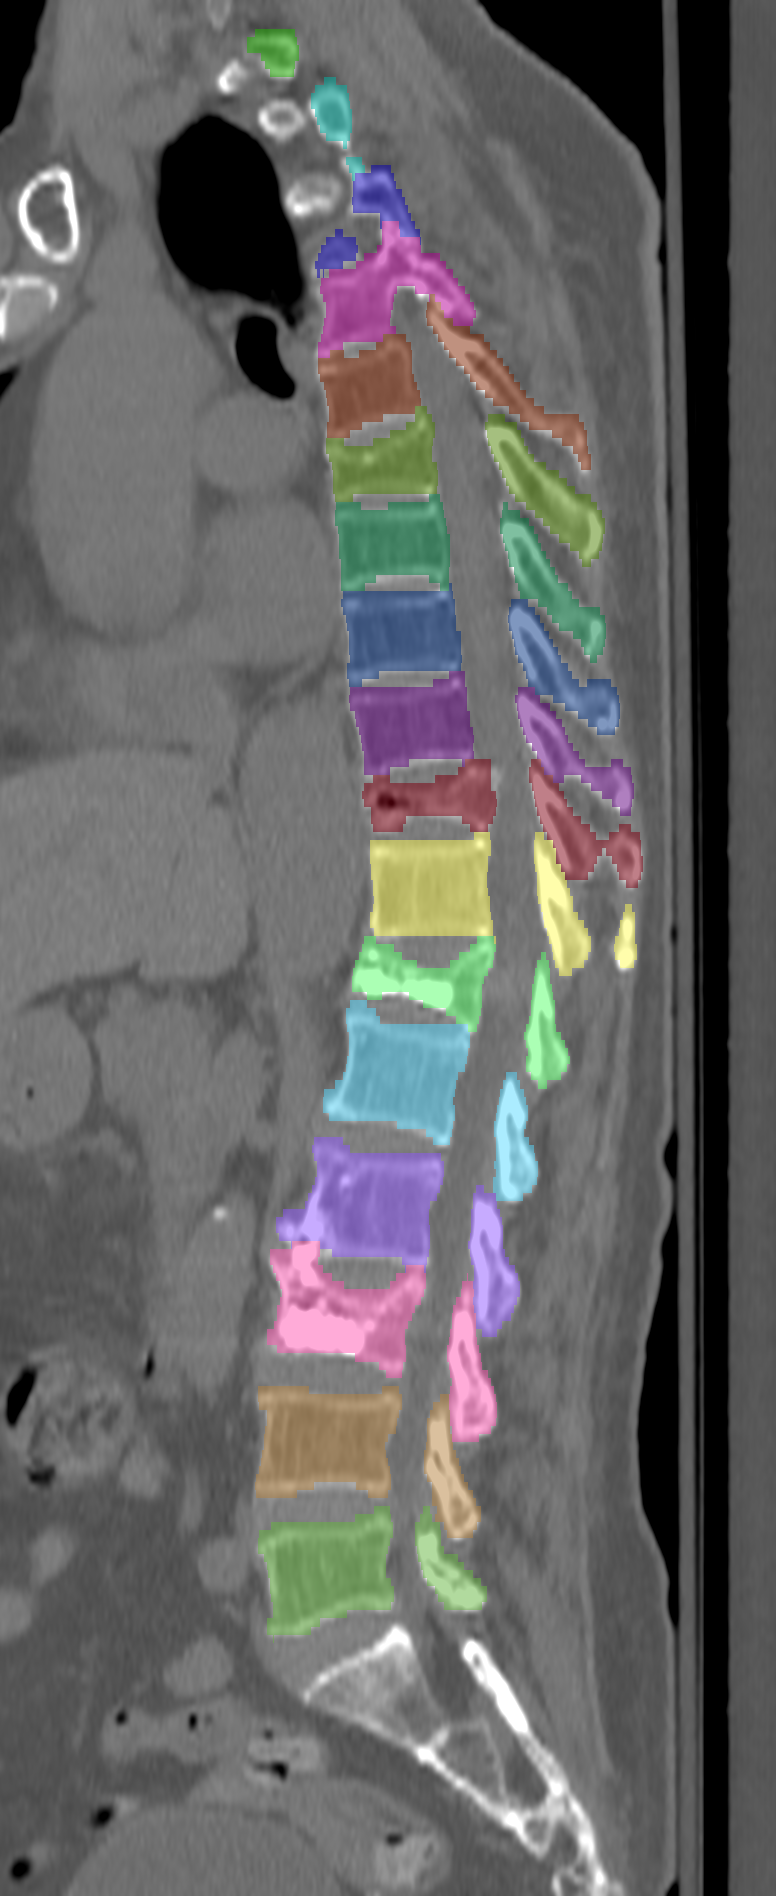

Normalized CT images and reference segmentations of thoracic and lumbar vertebrae from the CSI 2014 workshop

This is the dataset of the vertebra segmentation challenge of the CSI 2014 workshop that was held in conjunction with MICCAI 2014.

- Vertebrae have been anatomically labeled (8 = T1, 9 = T2, ..., 24 = L5)

- Because not always all visible vertebrae were segmented in the original data, only segmentations of the thoracic and lumbar vertebrae have been retained